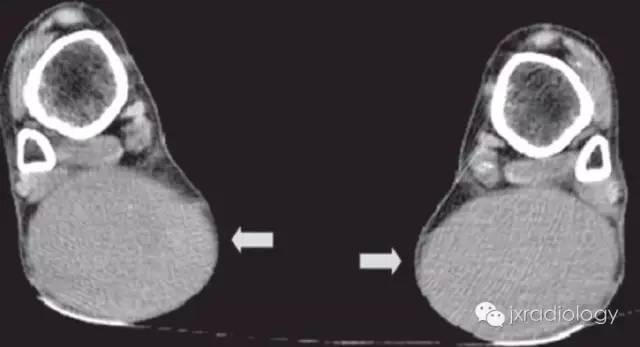

影像学表现:MRI典型病变的信号为跟腱明显梭形增粗 T1WI 像上呈顺跟腱长轴的类似肌肉的信号,表现为毛刷样改变,在 T2WI 像上也呈较低信号影,其内有斑点状短 T1 长 T2 较高信号影,T2WI 压脂像高信号区为低信号。CT:双侧跟腱部对称或单侧类梭形软组织肿块,向外膨隆,类似于肌肉密度,CT 值约 60~80Hu,与正常肌腱无法区分。